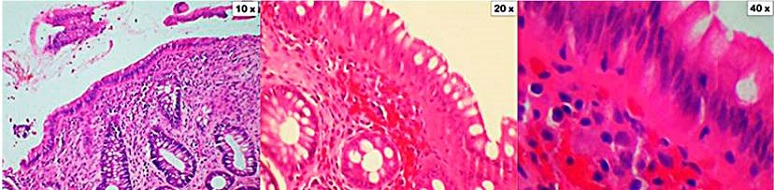

En el período de 22 meses comprendido entre febrero de 2018 y noviembre de 2019, se realizó en nuestra institución un total de 2849 colonoscopias por diferente diagnóstico. En 116 casos la indicación fue diarrea crónica, en todos los casos se tomaron biopsias y se contó con el informe histopatológico, con lo que se encontró un total de 15 pacientes con diagnóstico de CM (Figura 1), dado por el hallazgo de infiltración de linfocitos en la lámina propia, o por el engrosamiento de la capa de colágeno. De acuerdo con los criterios histológicos, se encontró algún tipo de colitis microscópica en el 12,9 % de los pacientes a quienes se les tomó biopsia por diarrea crónica (Figuras 2 y 3).

En la CL se observa una inflamación crónica de la lámina propia, dada por una proliferación de células plasmáticas, por la disminución de la cantidad de células caliciformes y por la infiltración de más de 20 linfocitos por cada 100 células epiteliales. En la CC hay un engrosamiento de la capa de colágeno, que sobrepasa el límite superior normal que es de 7 µm, aunque algunos autores consideran como diagnóstico el engrosamiento > 10 μm. Además de estos 2 subtipos histológicos, existe la CMI, que corresponde a la presencia de los síntomas clínicos sugestivos de la enfermedad, con hallazgos histológicos que no cumplen los criterios previamente mencionados. En estos casos, la cantidad de linfocitos y células plasmáticas es < 10/100 células epiteliales, y el colágeno subepitelial es < 10 μm. Estos hallazgos sugieren que las 2 formas clásicas de CM pueden no corresponder a 2 enfermedades diferentes, sino a 2 etapas diferentes en el desarrollo de una misma enfermedad5,10. Lo anteriormente descrito corresponde a los criterios diagnósticos empleados en el servicio de patología de nuestro hospital.

Al Dr. Jorge Monroy, jefe del Servicio de Patología del Hospital Central de la Policía, por su apoyo con las imágenes de histología